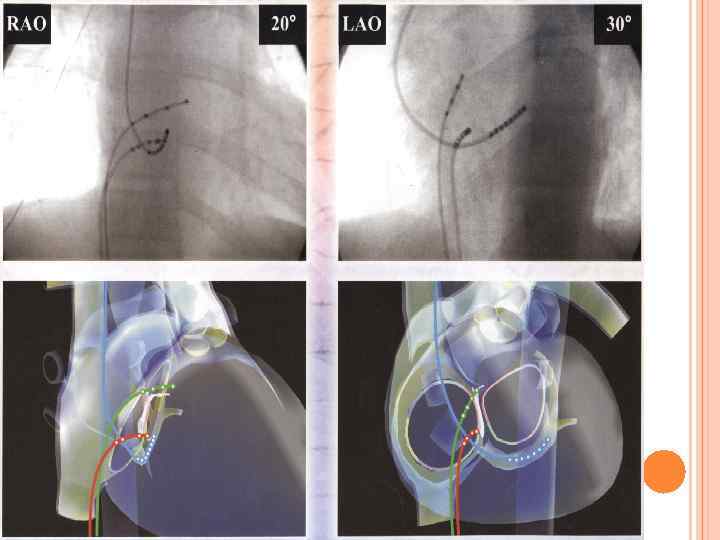

Стандартное расположение ЭФИкатетеров высокое ПП пучок Гиса правый желудочек венечный синус

РЧА

Система навигационного картирования CARTO

Эндокардиальная РЧ модификация операции «Лабиринт» с использованием системы Carto